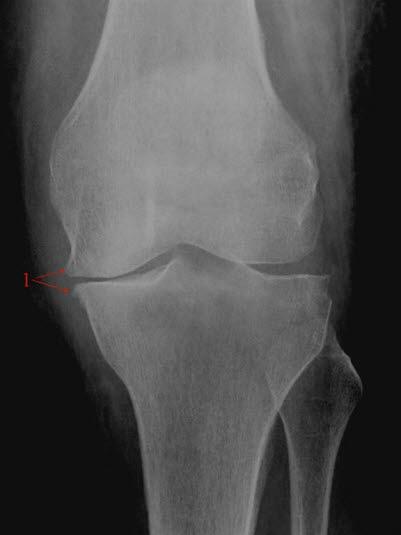

Røntgenbilde av kneleddetKneleddet utgjøres av lårbeinets og leggbeinets leddflater. Beinvevet er kledd med brusk som gjør at leddflatene glir mot hverandre med minst mulig motstand. I tillegg har kneleddet to bruskskiver (meniskene) som fremmer bevegeligheten i leddet. Artrose i kneleddet kalles det når leddbrusk eller bein i kneleddet er endret slik at overflatene ikke lenger er glatte og symmetriske. Dette kaltes tidligere slitasjegikt.

Røntgen av kneet viser typiske artroseforandringer (lette, moderate, uttalte artroseforandringer) og bekrefter diagnosen. Røntgenbildene forteller likevel ikke hele sannheten, fordi det kan være manglende samsvar mellom graden av plager og graden av forandringer på røntgen.